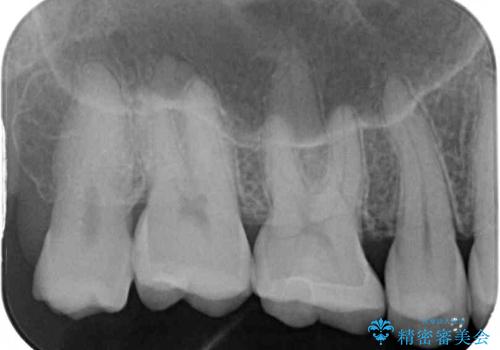

- 銀歯をセラミックにしたいとのことで来院された患者様です。

まず麻酔をして銀歯を外し、むし歯を除去し、形を整えて型取りします。